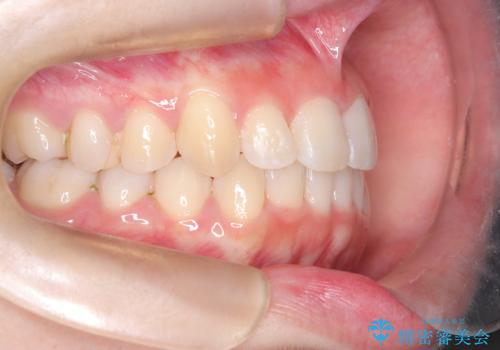

- 右上の前歯(2番)が下の歯より内側に入っている反対咬合を主訴にご来院されました。精密な検査の結果、この反対咬合を解消するためには、右上の歯列に前歯を出すためのスペースを確保する必要があると判明しました。患者様のご希望に合わせ、透明で目立たないインビザライン(マウスピース矯正)による治療計画を立案。奥歯全体を奥へ動かす遠心移動でスペースを作り、反対咬合を解消することを目指します。

今回の矯正治療では、透明なマウスピース型の装置インビザラインを使用しました。治療は、緻密なデジタル計画に基づき、奥歯から順に歯列全体を後方へ移動させる遠心移動を実施し、前歯を前に出すためのスペースを確保しました。このスペースを利用して、内側に入り込んでいた右上2番をスムーズに前方に誘導し、正常な咬み合わせへと改善。目立たないインビザラインで、機能的な咬み合わせと美しい前歯の並びを獲得していただけました。